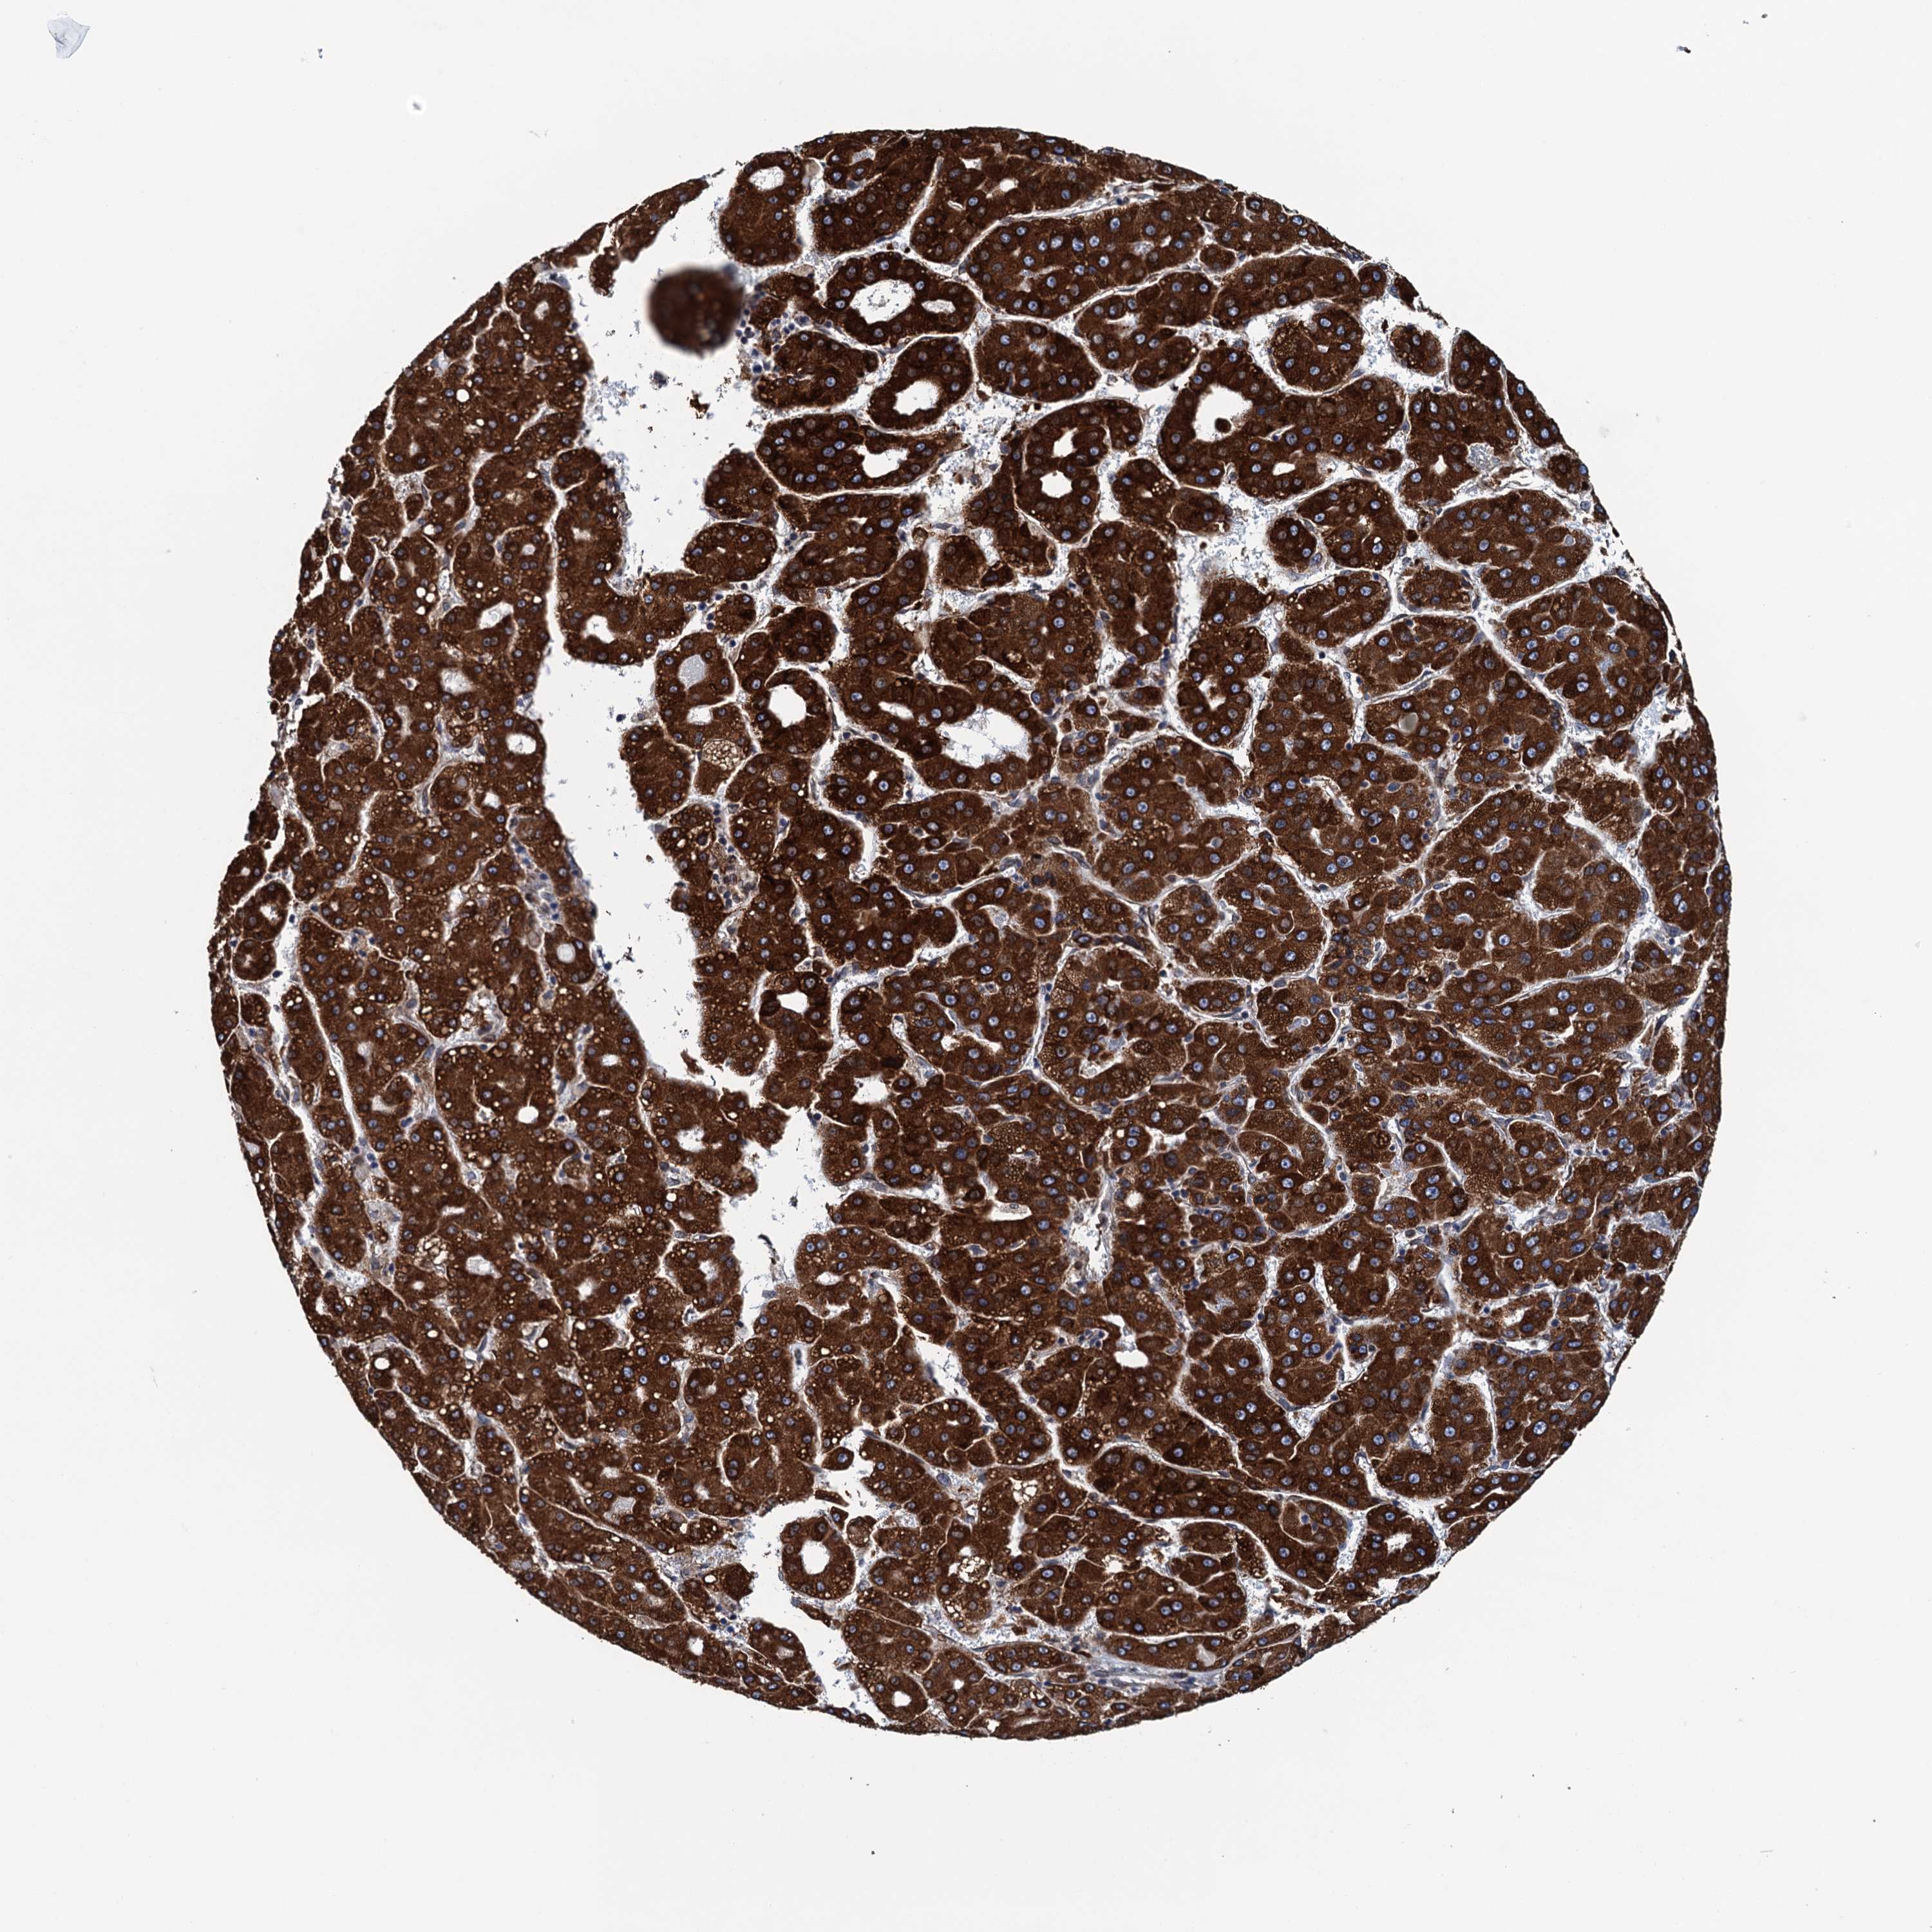

LIVER CANCER - Protein expressioni

A mouse-over function shows sample information and annotation data. Click on an image to view it in a full screen mode. Samples can be filtered based on level of antibody staining by selecting one or several of the following categories: high, medium, low and not detected. The assay and annotation is described here.

Note that samples used for immunohistochemistry by the Human Protein Atlas do not correspond to samples in the TCGA dataset.

Antibody stainingi

Antibody staining in the annotated cell types in the current human tissue is reported as not detected, low, medium, or high, based on conventional immunohistochemistry profiling in selected tissues. This score is based on the combination of the staining intensity and fraction of stained cells.

Each image is clickable and will lead to virtual microscopy that enables deeper exploration of all samples and also displays staining intensity scores, fraction scores and subcellular localization as well as patient and tissue information for each sample.

Antibody HPA041504

Staining

High

Medium

Low

Not detected

Intensity

Strong

Moderate

Weak

Negative

Quantity

>75%

75%-25%

<25%

None

Location

Nuclear

Cytoplasmic/membranous

Cytoplasmic/membranous,nuclear

Cholangiocarcinoma

Carcinoma, Hepatocellular, NOS